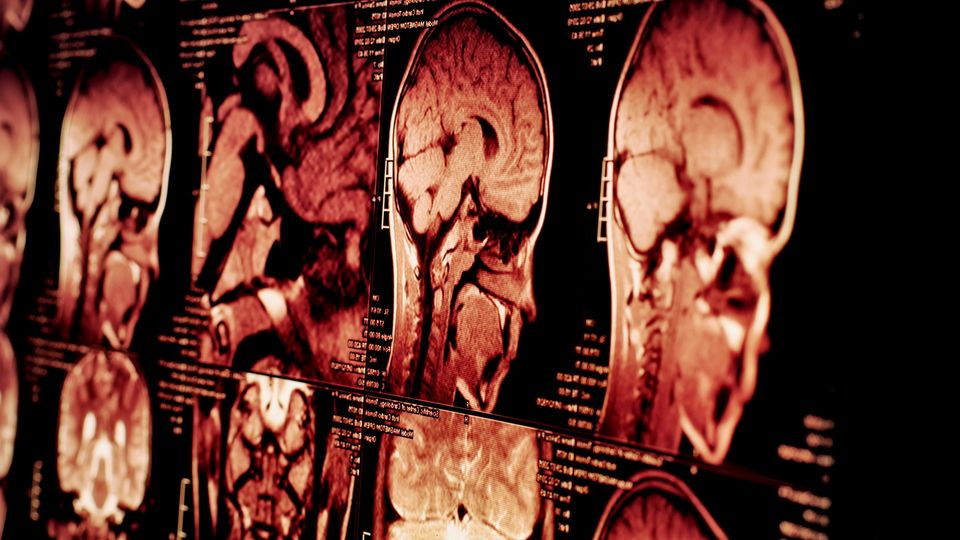

Series of brain MRI scans showing detailed cross-sectional views of brain structure and anatomy.

Credit: iStock.